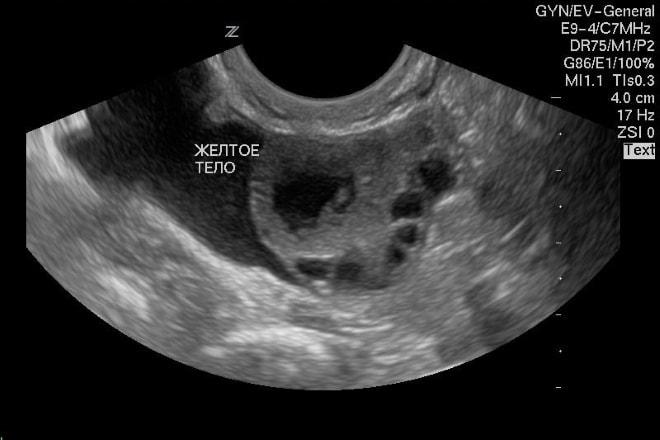

УЗИ желтого тела

Железо можно выявить с помощью УЗИ уже в первые дни его формирования. Оно выглядит как округлое образование с неоднородной структурой. Для его диагностики применяются трансабдоминальное или трансвагинальное УЗИ, то есть через брюшную стенку или с помощью введения датчика во влагалище. Процедура абсолютно безболезненна и безопасна, ее можно проводить на любом сроке беременности.

У девственниц и девушек гинекологическое УЗИ осуществляется через брюшную стенку.

Наличие желтого тела в яичнике может подтвердить беременность, но только после первых дней задержки менструации. Важно отличать его от кисты. Если железа обнаруживается в обоих придатках, это указывает на то, что овуляция произошла в обоих яичниках, что значительно увеличивает шансы на зачатие. При наличии персистирующего фолликула желтое тело в яичнике не визуализируется.

Однако отсутствие железа не всегда указывает на проблемы в организме. У многих женщин 1-2 раза в год наблюдаются ановуляторные циклы, что является нормальным явлением. Для подтверждения корректной работы придатков рекомендуется пройти повторное обследование в следующем месяце.

Сразу после овуляции, когда желтое тело только начинает формироваться в яичнике, врач может не увидеть его на УЗИ, поэтому диагностику лучше проводить через несколько дней после предполагаемого выхода яйцеклетки.